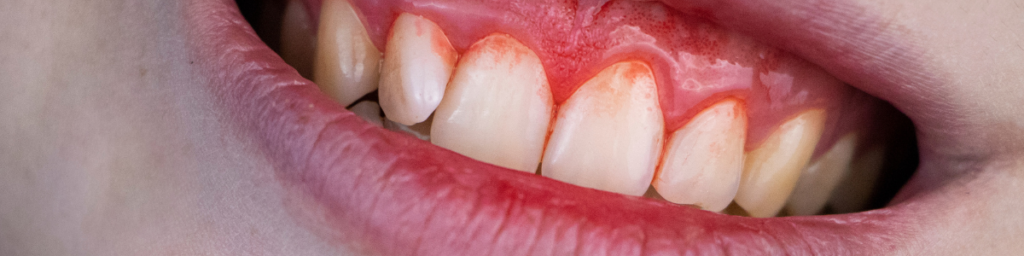

「歯磨きの時に少し血が出るだけ」「歯ぐきが時々腫れぼったい気がする」

歯周病はそのような、ごくわずかな自覚症状、あるいはまったく症状がないまま、静かにそして確実に進行していく病気です。

そのため、「サイレント・ディジーズ(静かなる病気)」とも呼ばれています。

そして、日本の成人が歯を失う原因の第一位。それがこの歯周病であるという重い事実があります。

痛みなどのはっきりとしたサインが出にくいがゆえに、多くの方がその深刻さに気づかないまま、歯を支える大切な顎の骨(歯槽骨)が静かに溶かされていく。

そして、「歯がグラグラする」「歯が長くなったように見える」といった明らかな異常に気づいた時には、すでに病状は深刻な段階にまで進行し、「もう抜歯しかありません」と告げられてしまう。